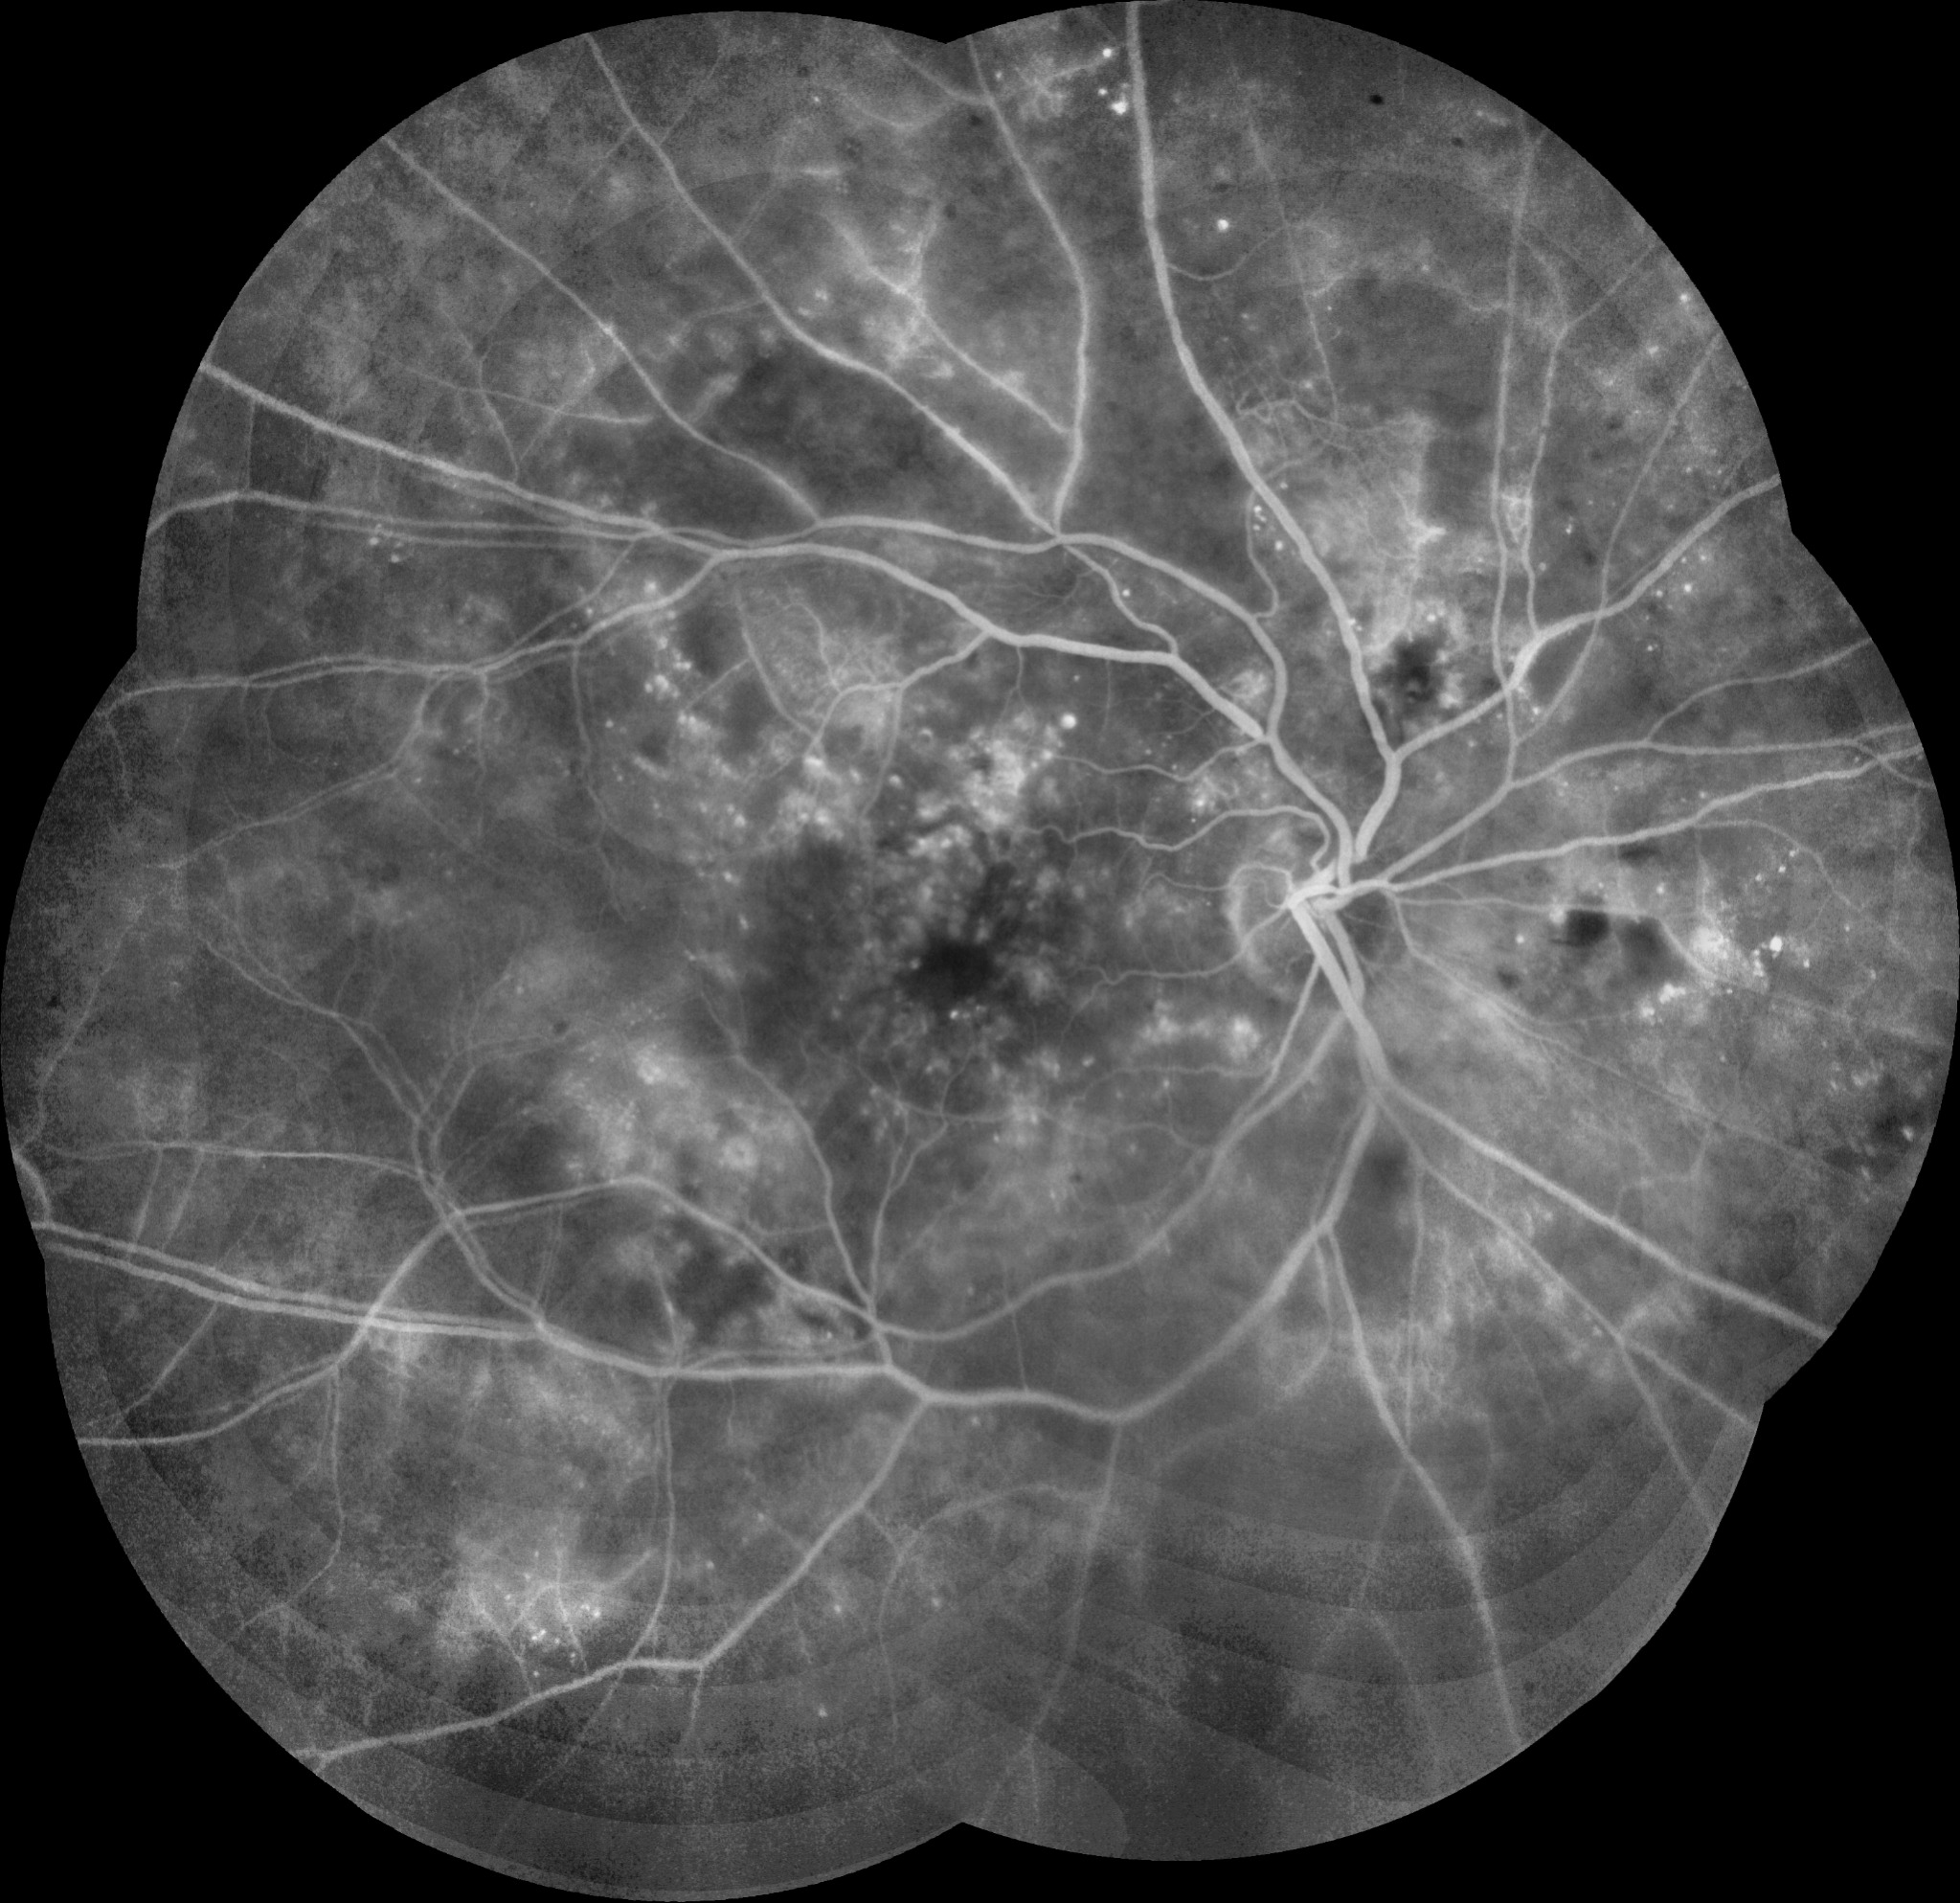

| RDP | ![]() | ![]() | Normal o EMD | Normal o engrosamiento coroideo | ![]() | LASER | Neovasos |

| RDP HV o HS | ![]() ![]() ![]() | ![]() ![]() ![]() | Normal o EMD | Normal o engrosamiento coroideo | ![]() | CIRUGIA: Vitrectomía + Endolaser | H Vítrea H Subhialoidea |